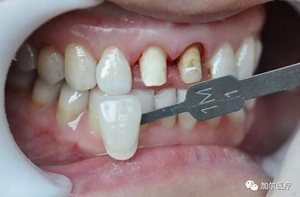

1、為什么有的人做完烤瓷牙還牙齦紅腫?

說明烤瓷牙邊緣不密合,除了材料,殘渣和致病菌都會刺激牙齦組織引起發(fā)炎,甚至影響到牙槽骨吸收,牙齦開始有逐漸退縮的趨勢,這時候你就可以看到黑黑的牙齦邊緣,一般醫(yī)生拆開烤瓷牙冠,前者材料倒還好,直接套上新牙冠,一段時間后牙

齦顏色恢復正常,不過后者原牙齲壞傷及牙髓就得根管治療。